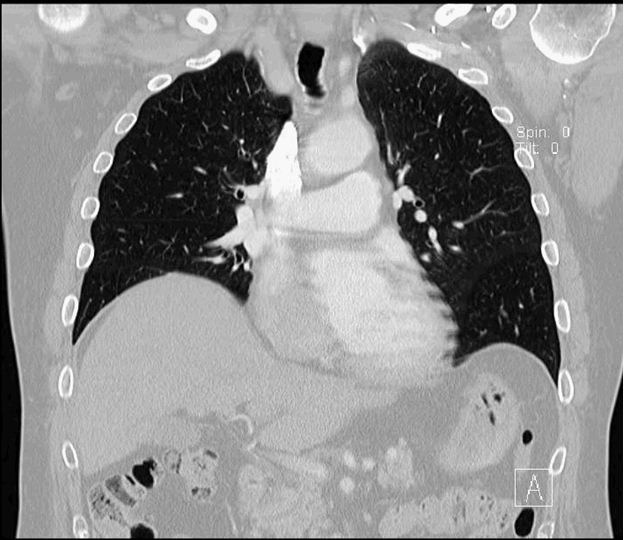

As workup for his dyspnea, the patient underwent pulmonary function testing, which showed a restrictive type of lung disease. A chest radiograph revealed an elevated right hemidiaphragm (Figure 1), which was confirmed by a CT scan (Figure 2). This raised the possibility of right phrenic nerve paralysis as the cause of his symptoms. There was no movement of the right hemidiaphragm observed during a sniff test, (Figure 3) which confirmed the diagnosis.

Figure 2.

Chest CT scan confirms right hemidiaphragm elevation.

There is no evidence of pulmonary embolism.